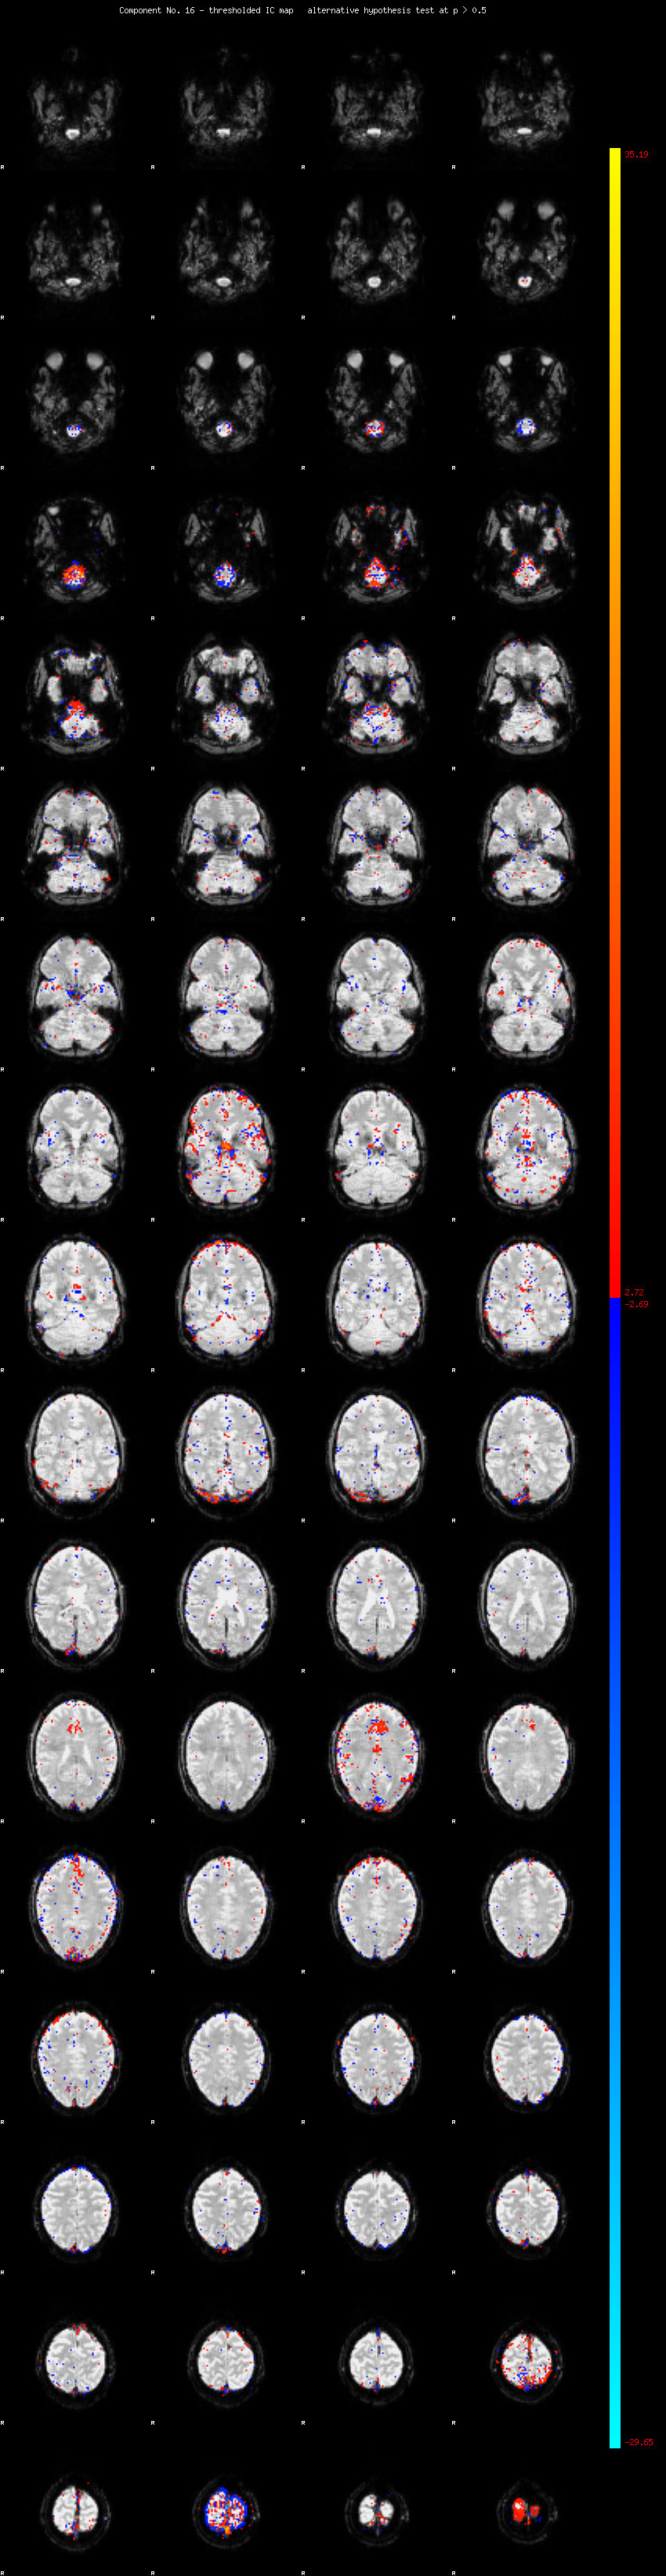

MELODIC Component 16

1.62 % of explained variance;     1.07 % of total variance